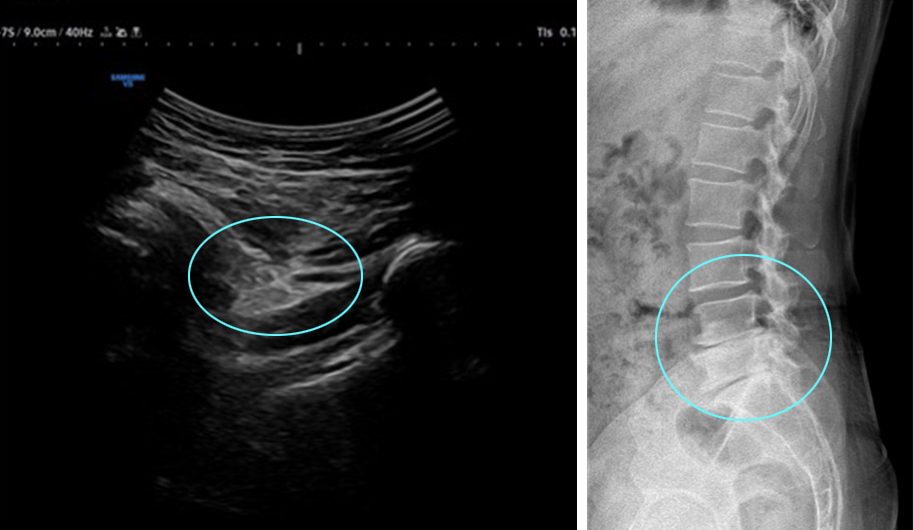

허리 협착 및 디스크 수술 후 허벅지 뒤쪽 및 내측으로 통증 지속되던 50대 환자.

좌골 신경에 하이펑쳐 주사 치료로 호전됨

조직재생 유도 물질로 잘 알려진 PDRN과

자하거(태반)를 환자별 맞춤 배합하여 초음파를 보며

고관절·허벅지 통증 병변에 주입